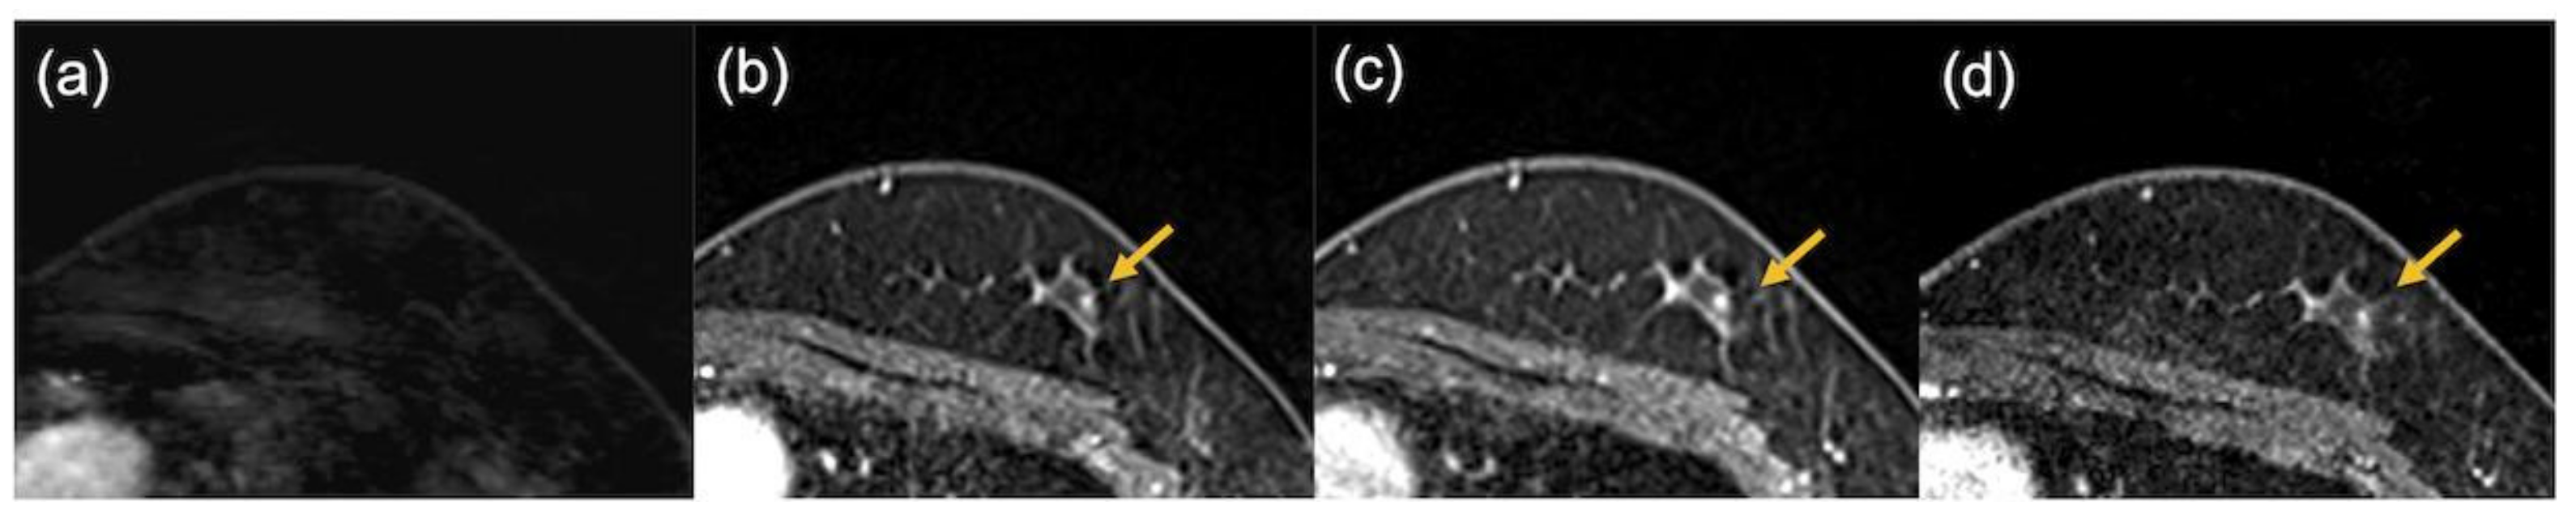

2.2. Image Evaluation